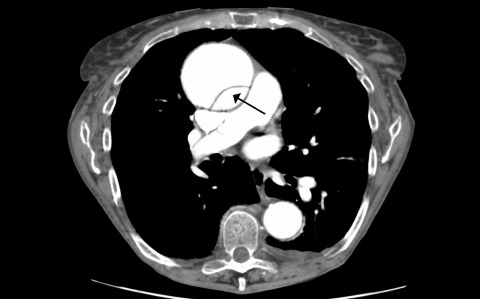

Ultrasound of Aortic Dissection

How to do a Point of Care Ultrasound (POCUS) to assess for aortic dissection. Presented by Dr. Jacob Avila, MD.

1 chapterMay 2017